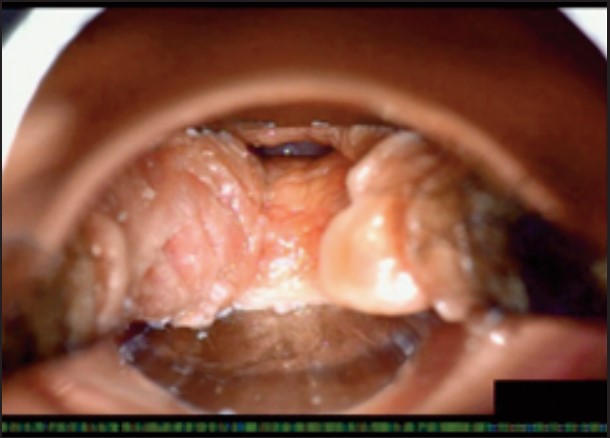

Під час спостереження до та після процедури, через 16 і 36 діб було зроблено вагінальні фотографії за допомогою Tele-Cervico (цервікографія) та виконано порівняння результатів до /після.

У пацієнток 1, 2 і 3 вагінальні складки утворилися та увиразнилися помітніше та сильніше, ніж вони були до лікування, ми оцінили цей клінічний результат після 1-го сеансу (через 16 діб). На нашу думку, такі виразні складки свідчать про підтяжку слизової оболонки піхви, що добре впливає на ущільнення піхви та проблему нетримання сечі. Через 36 діб після процедури ми спостерігали, що зруйнована анатомічна структура піхви відновила Н-подібну форму, тобто стала набагато здоровішою. Зокрема, у пацієнтки 4 структура піхви була цілковито зруйнована, стінки піхви обвисали через втрату еластичності. Однак через 36 днів після процедури структура піхви повністю відновила здорову Н-подібну форму [Див. Малюнок 3].

Пацієнтка №4

До

Після 36 діб

| Результати | √ Істотне відновлення H-подібної структури √ Зменшилася секреція √ Підтяжка |